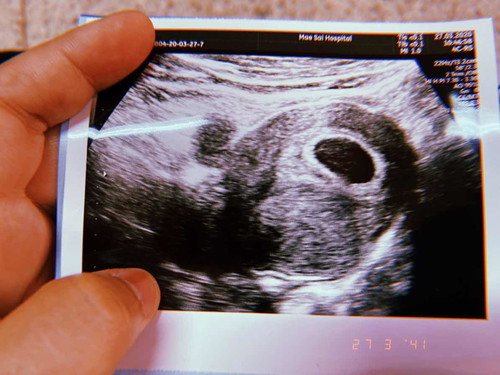

เดือนกว่าเห็นแต่ถุงตั้งครรภ์อยู่ค่ะ อีก2 อาทิตย์ไปใหม่จะมาอัพเดตให้นะคะ